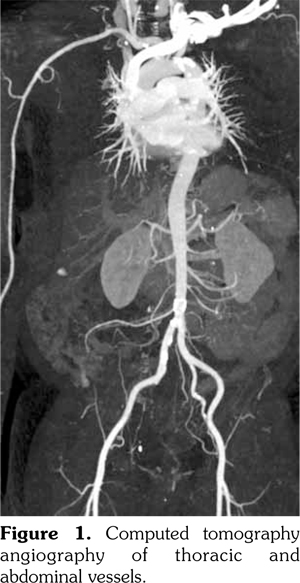

A 56-year-old male patient presented with high grade fever and headache for a month associated with proximal myalgias, right ankle synovitis, and bilateral orchitis. His general examination was remarkable for the thickened right superficial temporal artery with scalp tenderness. Lab tests revealed an erythrocyte sedimentation rate of 112 mm/at the end of 1st hour, a C-reactive protein level of 396.3 (<5) mg/L, normal liver and kidney functions, and an unremarkable urine microscopy. His anti- nuclear antibodies, cytoplasmic-anti-neutrophil cytoplasmic antibodies, perinuclear-anti- neutrophil cytoplasmic antibodies, and hepatitis serology were all negative. Ultrasound Doppler of the testes revealed increased vascularity suggestive of orchitis and funiculitis in both testes. Computed tomography angiography of thoracic and abdominal vessels revealed no evidence of vessel aneurysms or stenosis (Figure 1). The temporal artery biopsy (TAB) revealed dense mixed inflammatory infiltrate consisting predominantly of lymphocytes and histiocytes involving the tunica adventitia, and the media with an extension into the intima and near complete destruction of external elastic lamina and focal disruption of internal elastic lamina (Figure 2). There was no fibrinoid necrosis, leukocytoclasia or giant cells in the examined biopsy specimen. Patient was then treated with pulse intravenous methylprednisolone followed by oral steroids and methotrexate. Resolution of symptoms was noted over four weeks. Currently, after six months of follow-up, the patient is stable and on weekly subcutaneous methotrexate 20 mg along with prednisolone five mg/day. A written informed consent was obtained from the patient.